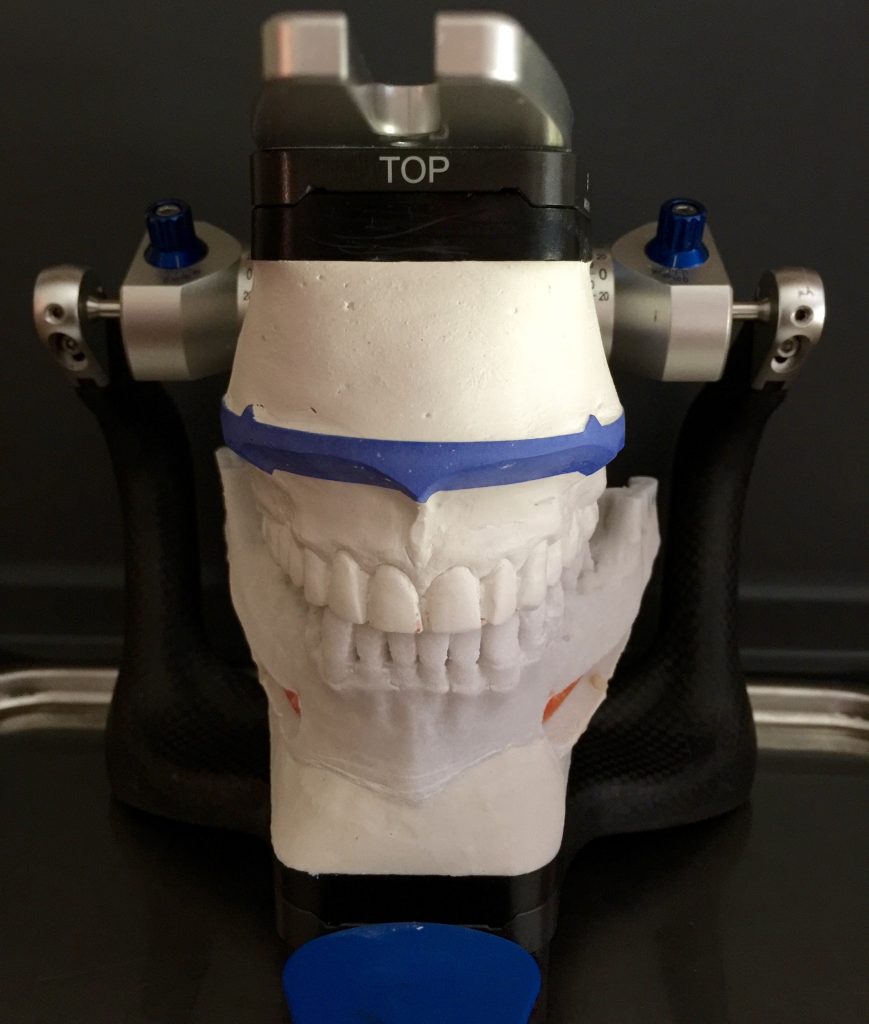

Autores: PRÓLOGO Asimismo, desde el punto de vista pedagógico, el profesional nobel en la materia tiene a su alcance la posibilidad de corregir cualquier posición implantaría en el ordenador, planear los provisionales y plasmarlos en la bio réplica antes de tocar al paciente a operar. Todos estos razonamientos nos llevan a presentar un caso de condiciones muy favorables para poner en práctica estos métodos como primer acercamiento a una Odontología Digital de alta calidad, con medios informáticos, que ya están presentes en la profesión de hoy en día, y será la protagonista única del futuro. Por otro lado, después de numerosos estudios que nos llevan a plantear el “gap” entre implante y pilar(abuttment), como principal responsable de la periimplantitis dado que la microbiota presente en el mismo es imposible de limpiar y en su presencia la cortical ósea reacciona reabsorbiéndose, nos ha llevado a utilizar implantes monobloc ya que los ejes implantarios y protéticos coincidían, y nos permitían su uso. Además, el circonio, ha mostrado a la luz de estudios muy recientes, una preservación y adhesión de los tejidos blandos superiores al titanio, tanto en su tratamiento de superficie de la rosca como a nivel gingival. DESARROLLO Paciente varón de 68 años, con antecedentes de radio/quimioterapia cinco años antes, con Rehabilitación Oral de los cuatro cuadrantes, con una Oclusión Mutuamente Compartida conservada, (REF.8) la que fracasa en el cuadrante 4, 19 años después. El mismo presentaba un puente de porcelana sobre circonio con pilares en 44 y 47, reemplazando el edentulismo de 45 y 46. Se produce la fractura del PM del 44, y ante una endodoncia antigua y corta, se decide implantar las zonas edéntulas, conservando temporariamente los pilares, hasta producida la oseointegración, para entonces también exodonciar el 44. DIAGNÓSTICO Tomamos impresiones del maxilar antagonista, Arco Facial Estático y realizamos montaje del mismo mediante la sistemática ARTEX. Producimos la relajación del músculo Pterigoideo Externo, para obtener la ORC (Oclusión en Relación Céntrica) mediante el método de Laminillas de Long, basado en el concepto de INERVACIÓN RECÍPROCA. Esto nos permitirá montar el maxilar inferior, tanto en su forma de: La primera para practicar la cirugía guiada y comprobar su eficacia, y el modelo de yeso para ser escaneado y confeccionar la GUÍA QUIRÚRGICA. La Biorréplica la obtenemos transformando los archivos DICOM que nos da el CBCT en archivos STL, y a partir de ellos, mediante una tecnología de PROTOTIPADO RÁPIDO, la obtención de un objeto físico en 3D a través de la aglutinación selectiva de una sucesión de capas de polvo. Procedemos a montar la biorrèplica y el modelo de yeso del caso. Podemos verificar la exactitud de las medidas del hueso residual en la bio réplica y compararlas con el scanner. Arrojando un resultado de 8,5 mm de cortical externa a cortical externa. Pudiendo también medir la distancia hasta el dentario. y comparar gracias a la ventana lateral de la biorréplica Dándonos 22mm de distancia. Con lo cual deducimos que implantes de 4,1mm por 12 mm serán perfectamente rodeados de hueso. Medimos también la distancia desde oclusal del antagonista, hasta el hueso desnudo. Lo mismo que, mediante la utilización de la guía radiológica, con un material radiolúcido colocado en gingival de la misma, podemos medir la altura de la encía. Con lo cual podemos calcular la altura del pilar. Es entonces cuando con el programa COC Diagnostix se realiza la programación final: Obteniendo no solo la ubicación, largo, ancho y ángulo de los implantes sino también los provisionales mediante CAD CAM. Ya entonces podemos hacer la práctica quirúrgica en la bio réplica, mediante la guía quirúrgica, instalando los implantes de prueba que no serán los de circonio, ya que la casa no cuenta con ellos, pero si otros de las mismas dimensiones. TRATAMIENTO Entramos ya en la cirugía propiamente dicha. Antisepsia de la zona a operar y zonas anexas. Comprobación del perfecto ajuste e inmovilidad de la G.Q. en boca durante la cirugía. Marcado de la encía y perforación de la cortical. Visión a través de la Guía de la mínima intervención anterior. Comprobación sin Guía. Incisión mínima mesio distal, para apartar y conservar encía queratinizada. Secuencia de drills, perforando a profundidad requerida Observación del Mínimo Trauma Implantes Strauman de Zirconio Monoblock en blíster y montádo en contrángulo reductor. Instalación controlando torque con contrángulo reductor. Comprobación clínica. Comprobación Radiográfica y con Guía. Toma de impresiones, y armado de modelos con técnicas de pasividad protética. Montaje. Resultado de las provisionales ejecutadas por CAD CAM Al no estar conformes con el resultado decidimos desechar dichas provisorias y optar por repetirlas. Nuevas provisorias realizadas mediante encerado convencional. Estado de los tejidos blandos. Provisorias en boca. Oclusión de Estímulo Inmediato. Ref.10: Carga inmediata .Alberto y Diego Bechelli. Comprobación mediante CBCT post operatorio Componentes del equipo (En la próxima presentación, mostraremos las coronas definitivas de porcelana sobre circonio, y la desoclusión provocada por una OCLUSIÓN MUTUAMENTE COMPARTIDA, sobre estos implantes y otros seis mas) REFERENCIAS

A-BIORRÉPLICA

Una vez obtenido el modelo matriz en polvo , se aplica un producto infiltrante para conferirle sus propiedades finales.

FIG: 14-15-16-17-18-19-20

FIG: 21-22-23-24-25-26

Fig. 21

Fig. 22

Fig. 23

Fig. 24

Fig. 25

Fig. 26

FIG:27